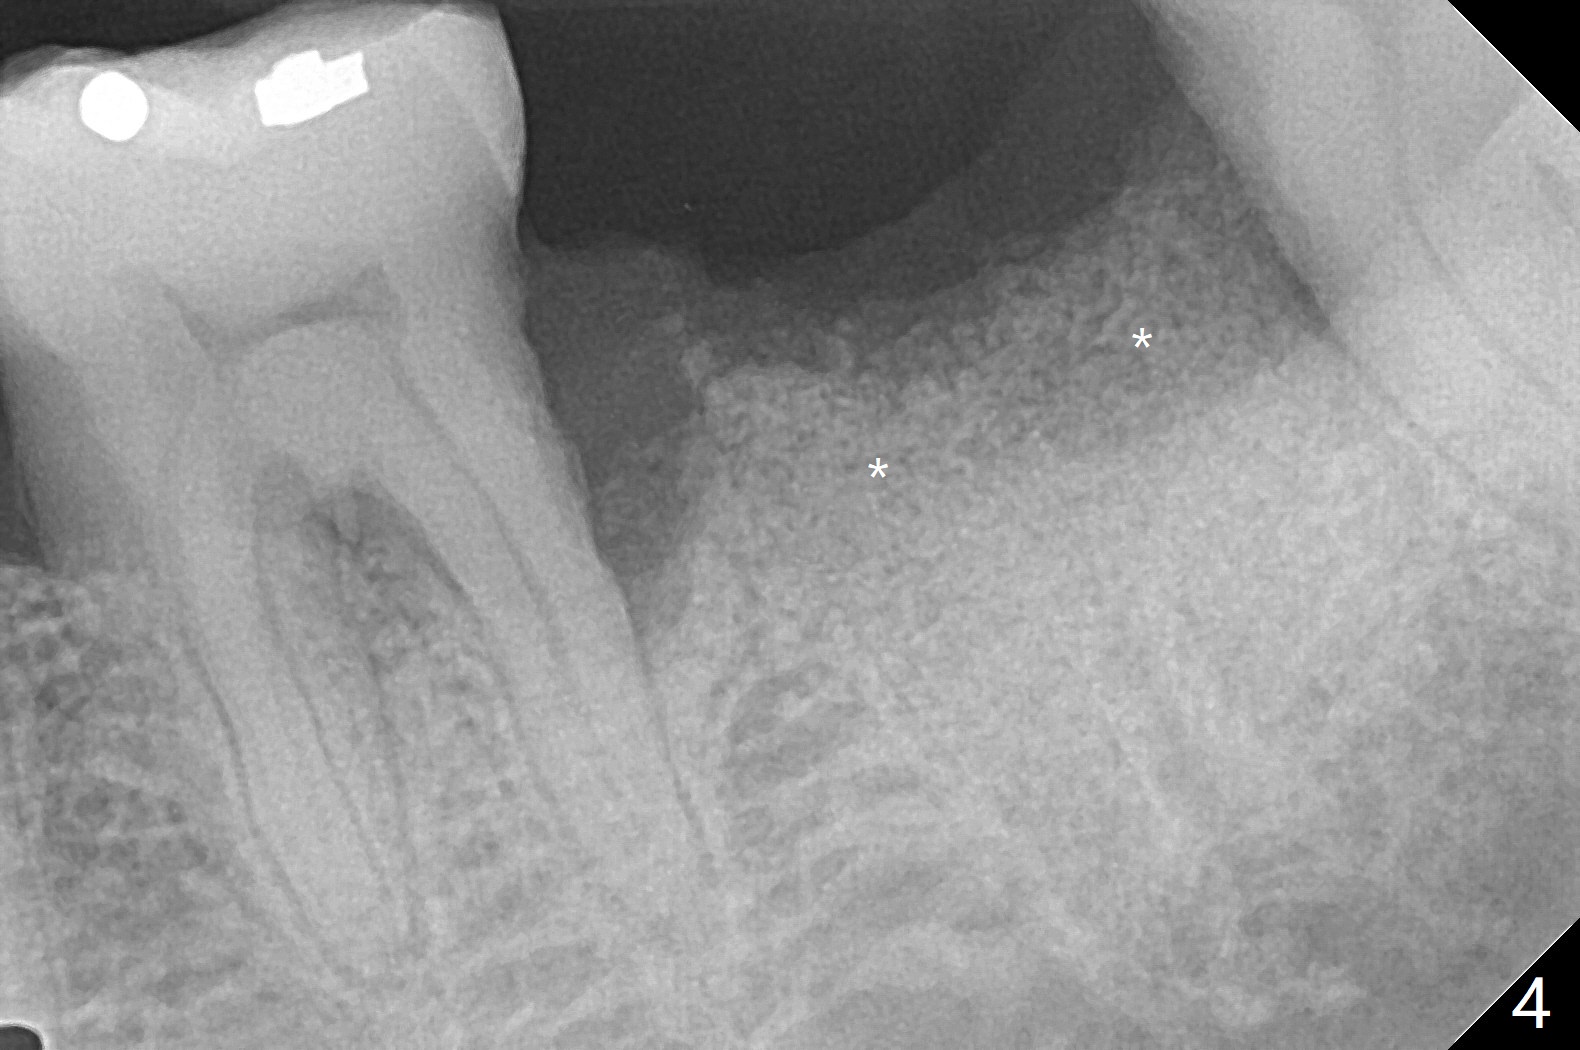

60岁男,吸烟,口腔卫生不好,不积极配合治疗,下前牙两个植体螺纹暴露,但是没有症状。两年中,左下七(图一,二)不能保留(图三),虽然六远中结石被清除(图三>),七位点保留(图四 *)时未能顺便在六远中填入骨粉(用血混合,胎盘膜覆盖)。四五个月后,七种植时将钻头骨粉放置于六远中缺损处,如何才能让骨粉在患处生根发芽?术后一个月,去除树脂敷料后,最表面骨粉未能被整合,下面骨粉好像已经与肉芽组织结合了(图五),其实根尖片应该拍摄证实这一点。吸烟者血供不好,愈合欠佳。术后三个月牙槽嵴宽(图六);高度稍微减低(图七)。术后4个月CT显示近中牙槽窝正好位于缺牙区正中(图八),所以植体必然进入近中窝(图九)。